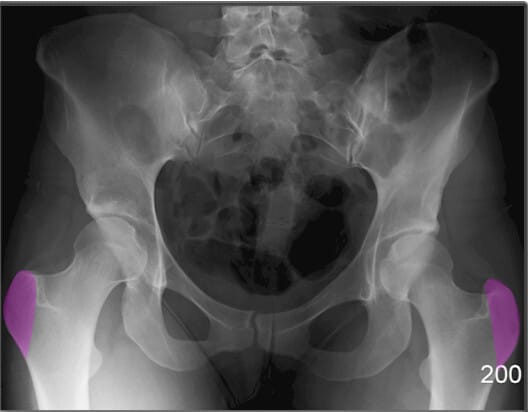

소전자 (Lesser Trochanter)

| 소전자 (Lesser Trochanter) |

| ✅ 대퇴골의 후내측에 위치한 작은 돌기이며, AP view에서는 보통 대퇴골 내측에서 작고 조밀한 음영으로 관찰됩니다. |

| 🔴 굴곡근(Hip Flexor)의 부착점이며, 과사용성 견열 손상이 발생할 수 있습니다. |